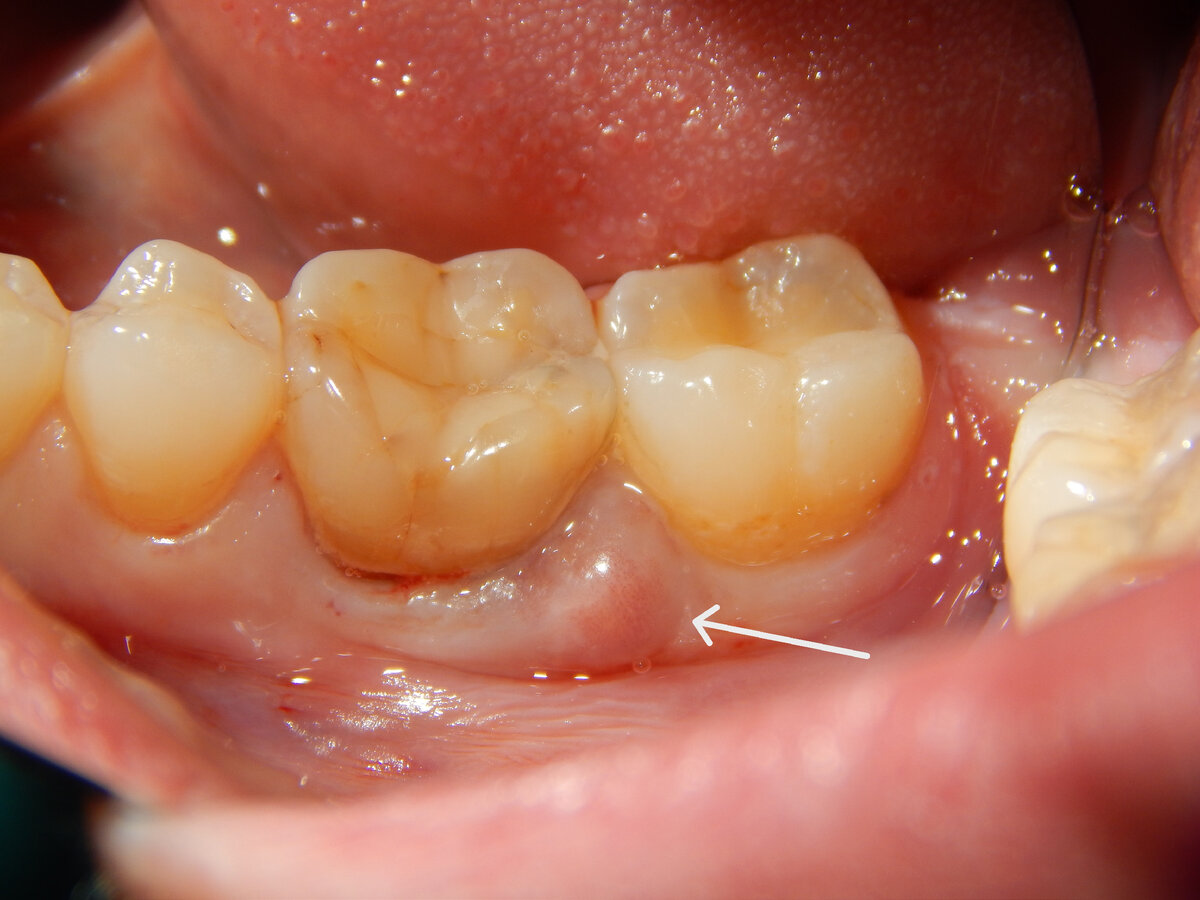

А всему виной явился вторичный кариес из-за него ткани зуба внутри стали полыми(пустыми) и при нагрузке (при пережёвывании пищи) возникла трещина корня.

Я нанёс раствор кариесиндикатора. И розовым остались прокрашены ткани, которые поражены.

От трещины корня, началось микровоспаление в близлежащей костной ткани и это привело к образованию шишечки с щёчной стороны. Инфекция нашла выход по пути наименьшего сопротивления в щёку.

То есть у пациента по факту была хроническая травма, некоторое время.

Каждый раз когда приходила (на этот треснувший зуб) жевательная нагрузка, фрагменты распирали костную ткань и микроорганизмы просачивались в костное русло.